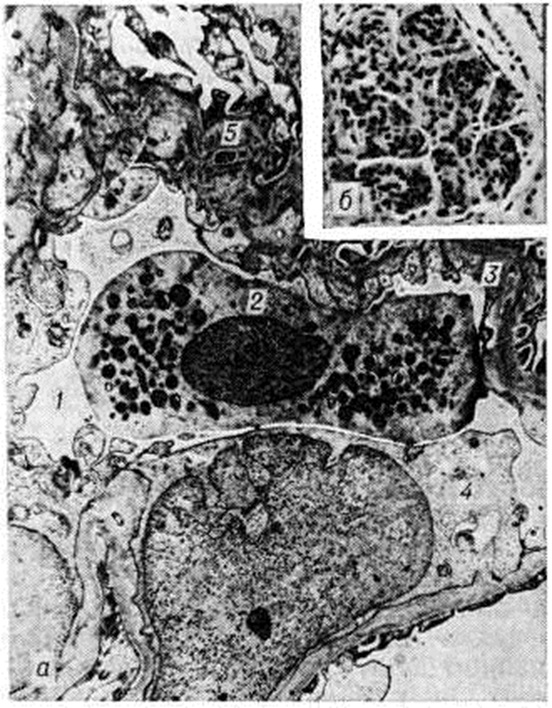

Реже ему предшествуют другие причины: пневмонии, пищевые токсикоинфекции, охлаждение, введение вакцины, сывороток, медикаментов и так далее. Реже ему предшествуют другие причины: пневмонии, пищевые токсикоинфекции, охлаждение, введение вакцины, сывороток, медикаментов и так далее. Типирование стрептококков, выделенных из зева больных Гломерулонефрит, показало, что в 78% случаев обнаруживается тип 12β-гемолитического стрептококка группы А. Преобладание 12 типа стрептококка отмечается как в спорадических случаях, так и при вспышках заболевания. В жарких странах развитию Гломерулонефрит особенно часто [в 85% случаев, по данным Диллона (Н. С. Dillon), 1967] предшествуют кожные болезни (пиодермия, импетиго, рожа); у таких больных, как правило, высеиваются пиогенные стрептококки. В сыворотке крови больных Гломерулонефрит наиболее часто обнаруживаются антитела к типу 12 стрептококка. Почти у 51% больных острым Гломерулонефрит стрептококковые антигены обнаруживаются в крови и выявляются в клубочках при иммунофлюоресцентной микроскопии [Сигал (В. С. Seegal), 1965; Андрес (G. A. Andres) с соавторами, 1966]. Часто обнаруживаются также антистрептолизин-О, антигиалуронидаза и антистрептокиназа. Однако постстрептококковый острый Гломерулонефрит с 50-х годы стал встречаться реже, что связано в значительной степени с применением мощных антибактериальных препаратов. Теснее связан со стрептококковой инфекцией Гломерулонефрит при подостром септическом эндокардите, что может проявляться не только классическим очаговым эмболическим нефритом [Лелейн (М. Н. F. Lohlein), 1910], но и диффузным поражением почек. Частота поражения почек при подостром септическом эндокардите может быть высокой — до 50%, при ревматизме (по секционным данным) — до 10,5%. Описан Гломерулонефрит и при стафилококковом эндокардите. Пневмонии осложняются Гломерулонефрит в 1—3% случаев. Роль брюшного и сыпного тифа, малярии в развитии Гломерулонефрит невелика. При малярийном нефрите находят отложение малярийного антигена в клубочках в составе иммунного комплекса наряду с иммуноглобулинами, комплементом, фибрином. При туберкулёзе клинический, картина Гломерулонефрит может оказаться ведущей. По данным В. В. Сура, А. М. Вихерта (1966), мембранозный Гломерулонефрит легко воспроизводится у животных при введении микобактериального адъюванта, то есть стимулятора процессов иммуногенеза (смотри полный свод знаний Адъюванты). Гломерулонефрит при туберкулёзе у человека описан Б. М. Коваливом и В. Ф. Подуговским (1957). Гломерулонефрит при сифилисе, протекающий обычно по нефротическому типу, редок. К инфекционно-иммунной группе Гломерулонефрит относят также малоизученные вирусные Гломерулонефрит при кори, ветряной оспе, вирусном гепатите, энтеровирусной инфекции. В группу Гломерулонефрит неинфекционно-иммунного происхождения входит Гломерулонефрит, развивающийся после ряда антигенных воздействий (сывороткой, вакциной, пыльцой растений, ядом насекомых, лекарственными и другими хим. веществами, пищевыми продуктами при индивидуальной непереносимости), а также Гломерулонефрит, возникающий при нарушении венозного оттока (частичный тромбоз почечных вен, нижней полой вены, сдавливающий перикардит, недостаточность трёхстворчатого клапана). Охлаждение, особенно при высокой влажности, может способствовать возникновению Гломерулонефрит или его обострению. ПатогенезОбщепринятой патогенетической классификации Гломерулонефрит пока нет. Наиболее обоснованной является иммуноаллергическая концепция, подтверждаемая клинический, иммунологический, экспериментальными и иммуногистохимический данными. Гломерулонефрит возникает обычно после инфекции или другого воздействия (вакцинация и так далее) при различной длительности латентного периода, хотя известно и его интраинфекционное развитие [Раммелькамп (С. Н. Rammelkamp), 1963]. В сыворотке крови больных Гломерулонефрит достаточно часто обнаруживают противопочечные антитела. Однако титры их не всегда коррелируют с клинический, проявлениями острого Гломерулонефрит, что позволяет ряду авторов рассматривать эти антитела как спутники процесса, не имеющие патогенетического значения. Титр комплемента при Гломерулонефрит почти постоянно снижен, что свидетельствует о потреблении комплемента в ходе иммунологический реакций. Гломерулонефрит легко воспроизводится в эксперименте с помощью гетерологических антипочечных сывороток, получаемых при иммунизации животных почечным антигеном животного другого вида [В. К. Линдеман, Масуги (М. Masugi)]. Как показали опыты с меченой противопочечной сывороткой, связывание ее на базальной мембране клубочков происходит в течение нескольких минут [Прессман (D. Pressman), 1948], возникновение клинко-морфологически проявлений Гломерулонефрит связано с фиксацией комплемента в клубочках и зависит от комплементсвязывающей способности вводимой противопочечной сыворотки. Для воспроизведения экспериментального Гломерулонефрит по Масуги используется противопочечная сыворотка птиц, не обладающая способностью связывать комплемент млекопитающих. Между введением сыворотки и возникновением Гломерулонефрит проходит латентный период (6—8 дней), необходимый для образования комплементсвязывающих противопочечных аутоантител. В патогенезе этого варианта экспериментального Гломерулонефрит можно выделить две иммунологический фазы — фиксацию экзогенных антител в почках и последующее образование аутоантител, способных связывать комплемент. Эксперименты с использованием адъювантов типа Фрейнда [Хейманн (W. Heymann), 1959] демонстрируют значение общей иммунологический реактивности для возникновения Гломерулонефрит. Если введение животным гомологичного почечного антигена не вызывает у них развития Гломерулонефрит, то введение его в составе микобактериального стимулятора позволяет воспроизвести Гломерулонефрит Иммуноаллергическая гипотеза патогенеза Гломерулонефрит подтверждается и данными, полученными при изучении роли стрептококков в его возникновении. Как показали опыты Кавелти (P. A. Cavelti, F. S. Cavelti, 1945), Гломерулонефрит удаётся вызвать введением животным смеси из ткани почки и стрептококков. Возможно, стрептококк меняет свойства белков ткани почки, делая их антигенными; не исключено и его адъювантное действие. Антиген стрептококка (М-протеин) по своей химических природе относится к гликопротеинам. Доказано антигенное сродство базальной мембраны капилляров клубочков и оболочек стрептококков нефрогенных штаммов. Часть М-протеина фиксируется в клубочках, часть циркулирует в кровяном русле, вызывая образование антител. Комплексы, образующиеся в результате реакции антиген—антитело, задерживаются клубочковым фильтром с фиксацией комплемента. Образование иммунных комплексов с фиксацией комплемента может происходить и непосредственно в клубочках. Иммунные комплексы повреждают почку. При иммуноморфологические изучении иммунокомплексного Гломерулонефрит скопления комплекса обнаруживаются субэндотелиально или субэпителиально в виде глыбок. Реже находят линейное расположение отложений (депозитов) иммунных комплексов, что свойственно для некоторых форм пролиферативного Гломерулонефрит, нефрита трансплантированной почки. В дальнейшем независимо от расположения депозитов в результате отчасти хемотаксического действия С3-комплемент системы (смотри полный свод знаний Комплемент) сегментоядерные лейкоциты фиксируются на капиллярных петлях, слущивают или отодвигают эндотелий, тесно контактируют с базальной мембраной. Лизосомальные ферменты лейкоцитов воздействуют на базальную мембрану и вызывают её повреждение. Участие клеточных механизмов иммунитета в патогенезе Гломерулонефрит, более характерных для мембранозного Гломерулонефрит, подтверждается возможностью переноса экспериментального адъювантного нефрита лимфоцитами (но не сывороткой) больного животного [Хесс (Е. V. Hess) с соавторами, 1962] здоровому реципиенту. Механизм такого переноса объясняется цитопатическим действием лимфоцитов в эксперименте [Холм (G. Holm), 1966], в том числе в культуре почечной ткани (Т. Г. Троянова с соавторами, 1973, 1974). Наряду с иммунными механизмами имеет значение сочетающееся с ними изменение процессов коагуляции; применение антикоагулянтов предупреждает при Масуги-нефрите тяжёлое поражение клубочков. Патологическая анатомияМорфологически изменения почек при Гломерулонефрит отличаются большим разнообразием и наблюдаются во всех их структурных элементах, но ведущим является диффузный гломерулит, в основе которого лежит воспаление обычно иммунной природы. Изменения клубочков при Гломерулонефрит были подробно изучены после внедрения в клинический, практику пункционной биопсии почки с использованием методов гистохимии (смотри полный свод знаний Гистохимические методы исследования), электронной микроскопии (смотри полный свод знаний), иммуногистохимии (смотри полный свод знаний Иммуноморфология), авторадиографии (смотри полный свод знаний) и другие. На основании изучения почечного пунктата [В. В. Серов, Нольтениус (Н. Noltenius), Диттрих (P. Dittrich), Бруэр (D. В. Brewer)] при Гломерулонефрит различают следующие изменения клубочков: минимальные, мембранозные, пролиферативные (интра и экстракапиллярные), экссудативные (интра и экстракапиллярные), мембранознопролиферативные, фибропластические. В этой классификации гломерулярных изменений, которая является дальнейшим развитием схем Эллиса (A. Ellis) и Белла (Е. Т. Bell), пролиферативные, мембранозные и фибропластические изменения — основные. Минимальные изменения (при световой микроскопии) сводятся к незначительному очаговому утолщению базальных мембран капилляров клубочков и гиперплазии клеток эндотелия лишь в отдельных петлях. Электронная микроскопия обнаруживает начальные изменения в виде редукции малых отростков подоцитов без выраженных изменений базальной мембраны капилляров клубочков [foot process type, по Чергу (J. Churg)]. Иммуногистохимический исследование даёт отрицательные результаты. О природе этих изменений единого мнения нет. Одни исследователи рассматривают их как проявление Гломерулонефрит, другие — как самостоятельное заболевание (липоидный нефроз детей). Мембранозный Гломерулонефрит (II тип по Эллису) описан впервые Беллом. Он предложил относить к мембранозному Гломерулонефрит клинический, случаи липоидного нефроза (идиопатический нефротический синдром), при к-рых гистологически обнаруживается утолщение (рисунок 1 в) и расщепление базальных мембран капилляров клубочков с наличием «шипиков», выявляемых методом серебрения, при отсутствии пролиферации клеток клубочка. В дальнейшем мембранозные изменения были обнаружены при гистологический исследовании почек (биопсия) не только при идиопатическом нефротическом синдроме, но и при других клинический, формах Гломерулонефрит. Исходным моментом в повреждении базальной мембраны капилляров клубочков считают фиксацию на ней аутологичных иммунных комплексов (рисунок 1 а), что доказывается методами иммуногистохимии (на базальных мембранах выявляются иммуноглобулины и комплемент) и электронной микроскопии (выявление депозитов на эпителиальной стороне мембраны). При мембранозном Гломерулонефрит, обозначаемом как диффузная мембранозная гломерулопатия (перимембранозный, или экстрамембранозный, Гломерулонефрит, липоидный нефроз взрослых), на наружной стороне базальной мембраны появляются гранулярные депозиты (рисунок 1 б) иммунных комплексов и отложения плазменных белков, тогда как внутренняя сторона мембраны имеет обычные контуры. Депозиты отделены друг от друга выступами lamina densa, направленными в сторону эпителия, в результате чего мембрана имеет вид гребня (мембранозная трансформация по Чергу). В результате «вымывания» депозитов базальная мембрана становится неравномерной плотности. Со временем между депозитами и ножками подоцитов образуются перемычки, они сливаются и уплотняются. Мембрана утолщается за счёт новообразованного слоя кнаружи от депозитов, которые инкорпорируются, подвергаются резорбции и становятся менее осмиофильными. При выраженных мембранозных изменениях пролиферация клеток клубочка отсутствует. Мембранозные изменения считаются морфологически эквивалентом идиопатического нефротического синдрома. Однако протеинурия при мембранозном Гломерулонефрит связана не только с изменениями клубочков, но и с недостаточной резорбцией белка в почечных канальцах. Морфология этой недостаточности представлена дистрофией и атрофией эпителия канальцев, склерозом стромы. Со временем дистрофические изменения почечных канальцев нарастают, выявляется гиалиноз мембран не только клубочков, но и канальцев. При пролиферативном Гломерулонефрит, развитие которого обычно связано с воздействием стрептококка, пролиферация эндотелиоцитов и мезангиоцитов, как правило, сочетается с экссудативными изменениями, инфильтрацией клубочка полиморфно-ядерными лейкоцитами. Отслаивая эндотелий, лейкоциты проникают к базальной мембране капилляров и мигрируют в мезангии (рисунок 2). Их постоянно можно найти рядом с гранулярными субэпителиальными депозитами в виде горбов («humps»), содержащими гетерологичные иммунные комплексы, в состав которых входят стрептококк, иммуноглобулин и комплемент. При электронной микроскопии депозиты иммунных комплексов обнаруживаются в биопсионном материале из почки через 2—4 недель от начала заболевания, но встречаются через 6 недель и более. С лейкотаксическим эффектом комплемента этих комплексов связана инфильтрация клубочка лейкоцитами, развитие иммунного воспаления в его соединительной ткани — мезангии. Повреждения базальной мембраны клубочковых капилляров также обусловлены литическим действием комплемента иммунных комплексов и лизосомальных ферментов лейкоцитов. В результате повреждения базальной мембраны и процессов внутрисосудистой коагуляции в капиллярах клубочков образуются тромбы, а также наблюдается реактивная пролиферация клеток клубочка. Пролиферация эндотелиоцитов сочетается с расширением мезангия, связанным с увеличением количества мезангиоцитов и накоплением мембраноподобного материала — мезангиального матрикса, что характерно для пролиферативного интракапиллярного диффузного Гломерулонефрит (мезангиопролиферативный Гломерулонефрит). Клинической, проявления интракапиллярного Гломерулонефрит различны, однако безусловна определённая зависимость между гематурией и выраженностью пролиферативной гломерулярной реакции. При преобладании пролиферации эпителия капсулы клубочка возникает пролиферативный экстракапиллярный Гломерулонефрит, который рассматривают как морфологически аналог злокачественного «подострого» или прогрессирующего острого Гломерулонефрит [Дженнингс (R. В. Jennings), Эрл (D. P. Earle)]. Этот вид Гломерулонефрит имеет достаточно характерную морфологию в виде так называемый полулуний из пролиферирующих клеток (рисунок 3 а), которые заполняют просвет капсулы и сдавливают капиллярные петли клубочка. Пролиферация клеточных элементов клубочков обычно сочетается с экссудативными экстракапиллярными процессами, появлением среди клеток нитей фибрина. При этом выявляется фагоцитарная функция подоцитов, в цитоплазме которых с помощью электронной микроскопии можно обнаружить множество фаголизосом (рисунок 3 б): перерабатывающих продукты белкового распада. Экстракапиллярная пролиферация возникает как реакция на резкое повреждение капиллярных петель клубочка, которое для экстракапиллярных форм Гломерулонефрит является правилом. Довольно рано клетки «полулуний» претерпевают фибропластическое превращение. В пролиферат врастает соединительная ткань со стороны капсулы, происходит рубцовая облитерация полости капсулы, что ведёт к гибели клубочка. Экссудативный (интра и экстракапиллярный) Гломерулонефрит как самостоятельная форма встречается крайне редко, что, вероятнее всего, связано с ранним лечением Гломерулонефрит стероидными препаратами. Обычно экссудативные изменения в виде скопления экссудата (серозного, фиброзного, геморрагического) в полости капсулы наслаиваются на морфологически проявления другой формы Гломерулонефрит, отражая остроту процесса. В ряде случаев они сочетаются с фибриноидным некрозом капиллярных петель клубочков, что позволяет говорить об экссудативно-некротическом Гломерулонефрит Мембранозно-пролиферативный Гломерулонефрит, хронический латентный или подострый нефрит, гипокомплементарный персистирующий, хронический лобулярный, смешанный, мезангиокапиллярный Гломерулонефрит — одна и та же форма, для которой морфологически характерны пролиферация мезангиоцитов и утолщение стенок капилляров клубочка [Камерон (J. S. Cameron) и соавторами, 1970], а клинически — хронический течение, протеинурия, реже гематурия и в ряде случаев отсутствие эффекта при лечении стероидными гормонами. Хотя за этим типом Гломерулонефрит и утвердился термин «мембранозно-пролиферативный», правильнее называть его мезангиопролиферативным [Мандаленакис (N. N. MandaJenakis) и соавторами, 1971], так как гломерулярные изменения при нем, в том числе и мембранозные, связаны прежде всего с пролиферацией мезангиальных клеток и интерпозицией мезангия. С помощью электронной микроскопии (рисунок 4 а) определяется резкое расширение мезангия за счёт пролиферации его клеток и увеличения матрикса. Расширение мезангия ведёт к его интерпозиции [Аракава и Киммелстил (М. Arakawa, P. Kimmelstiel), 1969] — отростки мезангиоцитов, окружённые мембраноподобным веществом, выходят за пределы соединительной ткани клубочка и, распространяясь вдоль базальной мембраны на периферию капиллярной петли, отодвигают эндотелий. При световой микроскопии выявляется феномен утолщения (рисунок 4,6) и расщепления мембраны. Пролиферация мезангиоцитов, наблюдаемая, как правило, вблизи депозитов иммунных комплексов, может быть ограничена эндотелиальной выстилкой (при этом просвет капилляра сохраняется свободным), либо пролиферирующие клетки прорывают эндотелиальную выстилку и заполняют частично или полностью просвет капилляра. Повышенная секреция пролиферирующими мезангиоцитами тропоколлагена ведёт к накоплению мембраноподобного вещества в стенке и просвете капилляров, что лежит в основе склероза и гиалиноза клубочков. Сужению просвета капилляров способствует также пролиферация эндотелия, однако она значительно уступает пролиферации мезангиальных клеток Изменения подоцитов разнообразны от гиперплазии ультраструктур, отражающей повышенную функциональную нагрузку, до глубокой дистрофии в виде редукции малых отростков, вакуолизации цитоплазмы, ворсинчатой трансформации клеток. Мембранозно-пролиферативный Гломерулонефрит делят на несколько клиническо-морфоиммунологических вариантов (форм): мембранозно-пролиферативный Гломерулонефрит с субэндотелиальными или плотными депозитами, лобулярный Гломерулонефрит, IgA-гломерулопатия (болезнь Берже). Мембранозно-пролиферативный Гломерулонефрит с субэндотелиальными депозитами характеризуется гиперплазией клеток мезангия, расщеплением базальных мембран гломерулярных капилляров (мезангиокапиллярный Гломерулонефрит), субэндотелиальными депозитами (содержащими большое количество иммуноглобулинов, ранние фракции комплемента, пропердин), гипокомплементемией. При мембранозно-пролиферативном Гломерулонефрит с плотными депозитами («болезнь плотных депозитов») гиперплазия мезангия представлена незначительно, и утолщение стенок капилляров обусловлено электронно-плотными депозитами внутри базальной мембраны. В депозитах обнаруживают большое количество С’З фракции комплемента, содержание которой в сыворотке крови снижено; иммуноглобулины в депозитах отсутствуют. О лобулярном Гломерулонефрит, который, как правило, является иммунокомплексным, говорят в тех случаях, когда пролиферация мезангиоцитов происходит в пределах дольки и сопровождается её ранним склерозом и гиалинозом. Основной признак IgA-гломерулопатии, или болезни Берже,— преобладание в субэндотелиальных и мезангиальных депозитах иммунных комплексов IgA и С’З фракции комплемента. Гистологически находят очаговую или диффузную пролиферацию мезангиальных клеток. Фибропластический Гломерулонефрит следует рассматривать как собирательную эволютивную форму пролиферативного, мембранозного и мембранозно-пролиферативного Гломерулонефрит. При всех этих формах Гломерулонефрит в развитии склероза и гиалиноза клубочков основная роль принадлежит мезангиальной трансформации: пролиферации мезангиоцитов, гиперпродукции мембраноподобного вещества и интерпозиции мезангия, ведущей к облитерации просвета капилляров (рисунок 5 а). Пролиферация и фибропластическая трансформация эндотелия в развитии гломерулосклероза играют меньшую роль. При фибропластическом Гломерулонефрит клубочки приобретают лапчатый вид (рисунок 5 б), нередко между капиллярными петлями и наружным листком капсулы клубочка появляются синехии. Некоторая часть клубочков полностью замещается соединительной тканью (гломерулосклероз, гломерулогиалиноз). При этом в эпителии главных отделов канальцев развиваются дистрофические и субатрофические изменения, возникает склероз сосудов и стромы почки. Чаще фибропластический Гломерулонефрит является результатом длительно текущего нефротического или гипертонического нефрита и, как правило, встречается при терминальной стадии заболевания. Морфологически формы, как и клинический., не являются стабильными. Они в ряде случаев отражают морфологию фаз и вариантов Гломерулонефрит Повторные биопсии почки доказывают возможность перехода одной формы Гломерулонефрит в другую. При Гломерулонефрит, кроме изменений в клубочках, возникают дистрофические и атрофические изменения в канальцах. При этом дистрофия преобладает в эпителии проксимального, а атрофия — в эпителии дистального отдела нефрона. Встречаются различные виды белковой дистрофии (зернистая, гиалиново-капельная, вакуольная) и жировая дистрофия. В основе её развития лежит повышение проницаемости гломерулярного фильтра, повышенная реабсорбция, инфильтрация почечных канальцев и блокада различных групп ферментов эпителия. Различные виды дистрофии эпителия канальцев отражают, таким образом, разную степень и различное качество развивающейся ферментопатии. В связи с этим зернистую дистрофию эпителия канальцев, при которой характер распределения дыхательных, гликолитических и гидролитических ферментов в нефроне не меняется, а активность их повышается, вообще не относят к патологический процессам. Считается, что зернистая дистрофия эпителия канальцев отражает морфологически повышенную реабсорбционную функцию канальца главным образом в отношении белка. Гиалиново-капельная, вакуольная и жировая дистрофии, при к-рых отмечается нарушение распределения ферментов в нефроне и снижение их активности, являются морфологически эквивалентами резорбционной недостаточности канальцев (относительной или абсолютной). Накопление в цитоплазме эпителия канальцев белка, воды или липидов ведёт к некробиозу и десквамации эпителия. Слущенный эпителий, как и компоненты ультрафильтрата, служит основой образования цилиндров, обтурирующих чаще дистальные отделы нефрона, что ведёт к повышению внутриканальцевого давления, образованию кистозно расширенных канальцев. При этом нередко отмечается регенерация эпителия целых отрезков канальцев. Атрофия канальцев, выраженная в той или иной степени, обычно дополняет дистрофические их изменения. Чаще всего это атрофия дистального отдела нефрона или группы нефронов, у которых клубочки гиалинизированы, склерозированы. Вокруг атрофичных, замещённых соединительной тканью нефронов происходит регенерационная гипертрофия соседних нефронов, которые могут длительное время обеспечивать функцию почки. Однако по мере прогрессирования Гломерулонефрит все чаще происходит «отрыв тубул» почечных канальцев от клубочков с образованием так называемый агломерулярных функционально неполноценных нефронов. Со временем атрофические процессы в почечных канальцах начинают преобладать над дистрофическими, все большее количество нефронов подвергается фиброзному замещению, конечным результатом которого является сморщивание почек. Значительные изменения происходят как в кровеносных, так и в лимфатических, сосудах почки. В кровеносных сосудах различают несколько видов изменений [А. И. Абрикосов, Цоллингер (Н. U. Zollinger)]: 1) пролиферативный эндартериит, касающийся артериол и мелких артерий, связанный, вероятно, с почечной аллергией при Гломерулонефрит [Фольгард (F. Volhard)]; в исходе этого процесса развивается склероз внутренней оболочки сосудов с резким сужением или облитерацией просвета сосудов; 2) плазморрагию, артериолонекроз и артериолосклероз (смотри полный свод знаний), обусловленные артериальной гипертензией; эти изменения наиболее ярко представлены при гипертоническом Гломерулонефрит; 3) гиперплазию внутренней оболочки, прогрессирующий интимофиброз средних и крупных артерий почки, нередко с вторичным липоидозом, атрофией средней (мышечной) оболочки и очагами аневризматического расширения просвета артерий; эти изменения рассматривают как приспособление артерий к выключению артериол и клубочков — «периферического русла почки». Изменения кровеносных сосудов ведут к редукции сосудистого русла, появлению «коротких путей» кровотока. В корковом веществе увеличивается количество коротких ветвей, связывающих в обход клубочка приносящую и выносящую артериолы, уменьшается число постгломерулярных (перитубулярных) капилляров коры, как и ложных прямых артерий, питающих мозговое вещество почки. Запустевает не только кровеносная, но и лимфатических, система. Недостаточность лимфатических, системы наступает вторично, прежде всего в связи с нарушениями почечного кровообращения. Редукция кровеносного и лимфатических, русла почек способствует развитию в них склеротических и атрофических изменений. В строме почек развиваются отёк, склероз, липоидная и клеточная инфильтрация. Отёк резче выражен в мозговом веществе и служит основой рано наступающего гиалиноза пирамид, особенно их сосочков (смотри полный свод знаний Гиалиноз), что имеет значение в развитии нарушений противоточного механизма почки. Склероз, как и отёк, раньше наступает и резче выражен в мозговом веществе почек, где он имеет диффузный характер. В корковом веществе, помимо диффузного фиброза стромы, отмечают очаги склероза, замещающие группы выключенных нефронов. Со временем очаги склероза сливаются, образуя фиброзные поля, в которых замурованы гиалинизированные клубочки и атрофированные канальцы. По периферии таких полей сохраняются гипертрофированные нефроны (регенерационная гипертрофия). В ряде случаев (при нефротическом синдроме) в склерозированной строме почек находят в большом количестве двоякопреломляющие липоиды (липоидная инфильтрация стромы). Склероз стромы, как правило, сочетается с клеточной инфильтрацией, представленной гнездными скоплениями лимфоидных элементов, гистиоцитов, плазматических клеток. Считается, что гистиолимфоцитарные инфильтраты стромы могут отражать иммунные реакции (замедленную гиперчувствительность), развивающиеся в почках при Гломерулонефрит. В пользу этого предположения свидетельствует способность клеток инфильтратов к цитопатогенному действию, проявляющемуся лизисом мембран и эпителия канальцев. Не исключено, что лимфоидные инфильтраты стромы всего лишь адаптивная реакция клеток мезенхимы на развивающуюся резорбцию и механическую недостаточность лимф, системы почки. При остром гломерулонефрите в первые дни заболевания наблюдается гиперемия клубочков, которую довольно быстро сменяют лейкоцитарная инфильтрация мезангия и диффузная интракапиллярная пролиферация клеток (интракапиллярный экссудативно-пролиферативный Гломерулонефрит), тромбоз отдельных капиллярных петель, плазматическое пропитывание и фибриноидные изменения артериол. В дальнейшем присоединяются экстракапиллярные экссудативные изменения в виде серозно-десквамативного, фибринозного или геморрагического выпота в полость клубочковой капсулы (экссудативный экстракапиллярный Гломерулонефрит) или пролиферация нефротелия при резком повреждении базальной мембраны капилляров клубочков. В более тяжёлых случаях (смерть в первые недели заболевания) наблюдается острый некротический Гломерулонефрит, для которого характерен фибриноидный некроз петель капилляров клубочка и приносящей артериолы наряду с тромбозом капилляров и инфильтрацией нейтрофильными лейкоцитами. Очень редко развивается типичный мембранозный Гломерулонефрит Почки при остром Гломерулонефрит несколько увеличены, набухшие, дрябловаты, пёстрые — «пёстрая почка» (цветной рисунок 5). Пирамиды темно-красные, кора серовато-коричневого цвета с мелкими красными вкраплениями на поверхности и разрезе — при геморрагической форме или с сероватыми полупрозрачными точками — при пролиферативной и фибринозной экссудативной формах. Однако в ряде случаев (смерть в первые дни болезни) почки при вскрытии могут казаться совершенно неизмененными, и лишь гистологический исследование выявляет диффузный Гломерулонефрит На основании изучения повторных биопсий выявлено, что изменения почек, характерные для острого Гломерулонефрит, могут быть полностью обратимы. Но в ряде случаев даже при полном клинический, выздоровлении гистологический изменения, свойственные Гломерулонефрит, могут сохраняться годами. Для подострого гломерулонефрита, быстро прогрессирующего, или злокачественного, характерно сочетание экстракапиллярных продуктивных (реже экссудативных) изменений клубочков с тяжёлыми дистрофическими изменениями канальцев (подострый Гломерулонефрит с нефротическим компонентом, по старым авторам) и отечно-инфильтративными изменениями стромы. Почки при этом значительно увеличены, дряблы, корковый слой широкий, набухший, жёлто-серый, тусклый, с мелкими красными вкраплениями и хорошо отграничен от темно-красного мозгового вещества почки — «большая пестрая почка» (цветной рисунок 7) — либо он красный и сливается с полнокровными пирамидами — «большая красная почка». Морфология хронического гломерулонефрита весьма разнообразна, обнаруживаются интракапиллярные пролиферативные, минимальные, мембранозные, мембранозно-пролиферативные, а также фибропластические изменения в различных сочетаниях с изменениями канальцев, сосудов и стромы. Чёткой зависимости между клинический, вариантами и морфологически формами при хронический Гломерулонефрит нет. Однако можно считать, что для гематурии (гематурический вариант Гломерулонефрит) наиболее характерны интракапиллярные продуктивные процессы в клубочках, для протеинурии (нефротический вариант хронический Гломерулонефрит)— минимальные и мембранозные изменения, к к-рым присоединяется тубулоинтерстициальная недостаточность, а для артериальной гипертензии (гипертонический вариант хронический Гломерулонефрит) и сочетания нефротического синдрома с гипертензией — фибропластическая реакция в клубочках и вторичные васкулярно-интерстициальные изменения. Наиболее характерные макро-, микроскопические изменения почек наблюдаются при нефротическом варианте хронический Гломерулонефрит и в терминальной стадии заболевания. При нефротическом варианте Гломерулонефрит в ряде случаев дистрофические изменения канальцев и стромы почек, особенно жировая инфильтрация, доминируют над минимальными или мембранозными изменениями клубочков. Почки при этом становятся увеличенными, дряблыми, бело-жёлтыми или белыми — «большая белая почка» (цветной рисунок 6), и их трудно отличить от липоидного нефроза (идиопатического нефротического синдрома). Для терминальной стадии хронический Гломерулонефрит характерно развитие вторичного (нефритического) сморщивания почек. При этом почки уменьшаются в размерах, становятся плотными, поверхность их мелкозернистая, редко гладкая — при равномерном сморщивании (цветной рисунок 9). Зернистость поверхности почек объясняется тем, что участки склероза и атрофии (западания) чередуются с участками гипертрофированных нефронов (выбухания). На разрезе слой почечной ткани тонкий, причём особенно истончено корковое вещество; ткань почки суха, малокровна, серого цвета (цветной рисунок 10). При микроскопическом исследовании в запавших участках отмечаются атрофия клубочков и канальцев и замещение их соединительной тканью (цветной рисунок 8). Клубочки превращаются в рубчики (гломерулосклероз) или гиалиновые шарики (гломерулогиалиноз). В выбухающих участках клубочки сохранны, некоторые из них гипертрофированы. Капсула таких клубочков утолщена, капиллярные петли склерозированы (лапчатые клубочки), кое-где встречаются склерозированные «полулуния», канальцы расширены, эпителий их утолщён. Артериолы склерозированы и гиалинизированы. В мелких, средних артериях наблюдаются фиброз и гиалиноз внутренней оболочки, резко выражены склероз и гистиоцитарная инфильтрация стромы. Клиническая картинаОстрый гломерулонефрит может развиться в любом возрасте, однако до 2 лет он встречается редко [Фисон (Т. N. Fison), 1956]. Показатели заболеваемости колеблются от 0,55 до 0,71, а среди различных детских возрастных групп от 0,08 до 0,85 на 1000 человек. Максимальная заболеваемость среди детей приходится на возраст от 7 до 10 лет (Н. А. Чистенков, 1969). Среди взрослых показатели заболеваемости в среднем 0,62 на 1000 (А. М. Шухтина и А. Н. Бутц, 1963); больные моложе 40 лет составляют 75—90% [В. В. Пожарская, М. С. Бабицкая, 1936; Аддис (Т. Addis), 1948]; больные старше 60 лет составляют не более 3%. Различий заболеваемости мужчин и женщин не выявлено. Клинической, проявления острого Гломерулонефрит весьма разнообразны — от крайне скудных (лишь случайно в процессе обследования выявленные изменения мочи) до чрезвычайно ярких, с бурно развивающейся классической триадой симптомов: отёков, гипертензии, гематурии. Этим симптомам может предшествовать слабость, жажда, олигурия. При развившейся картине болезни больного беспокоит одышка, сердцебиение, головная боль, тошнота, рвота, боли в пояснице, отеки разной степени выраженности. Моча при макрогематурии может быть красной или коричневатой из-за перехода гемоглобина в гематин при кислой реакции мочи. Отеки — один из наиболее ранних и частых признаков Гломерулонефрит— отмечаются у 70—90% больных, приблизительно у половины они бывают значительными. Преимущественная локализация отёков на лице, бледность кожи и набухание шейных вен позволяют говорить (у части больных) о facies nephritica. Отеки могут начинаться и на ногах. В отёчной жидкости белка до 1—2%. Патогенез отёков при остром Гломерулонефрит сложен и до конца не ясен. Первопричиной их является поражение клубочков, ведущее к уменьшению клубочковой фильтрации, что сопровождается снижением диуреза (смотри полный свод знаний). Повышается реабсорбция натрия (и воды) в канальцах. Роль гиперальдостеронизма при этом исключить трудно; хотя секреция альдостерона обычно не повышена, но натрийуретический и диуретический эффект антагонистов альдостерона очевиден. В возникновении отёков придаётся значение увеличению сосудистой проницаемости. Артериальная гипертензия регистрируется у 70—90% больных (смотри полный свод знаний Гипертензия артериальная). Степень её значительно колеблется, частота возникновения и тяжесть увеличиваются с возрастом. Гипертензия, как и другие симптомы острого Гломерулонефрит, может быть «транзиторной». Снижение АД до нормального уровня происходит обычно на протяжении первых 3 недель параллельно с уменьшением других симптомов. Длительное и стойкое повышение АД прогностически неблагоприятно. Ведущее значение в патогенезе гипертензии при остром Гломерулонефрит придаётся задержке натрия и воды, увеличению объёма циркулирующей крови и ударного объёма сердца. Повышение АД по гиперкинетическому типу с увеличением сердечного выброса сочетается со снижением периферического сопротивления в первые дни заболевания. В дальнейшем по мере снижения АД периферическое сопротивление нормализуется (М. И. Франкфурт, А. К. Мерзон, 1968). При тяжёлом течении Гломерулонефрит выявляется стойкое увеличение периферического сопротивления. Значение системы ренин — ангиотензин в возникновении гипертензии при остром Гломерулонефрит подвергается изучению. Не исключена большая чувствительность сосудистой стенки к прессорным агентам в связи с задержкой в ней натрия. Частота гемодинамических нарушений увеличивается с возрастом. Явления сердечной недостаточности, острый отёк лёгких являются основной причиной смерти больных острым Гломерулонефрит Обычны характерные признаки левожелудочковой (одышка, ортопноэ, кровохарканье, сердечная астма, достигающая значительной степени) и правожелудочковой недостаточности (набухание шейных вен, повышение венозного давления). В основе возникновения гемодинамических нарушений лежит увеличение массы циркулирующей крови, которая может достигать 7—9 литров. При отсутствии гиперволемии гемодинамические сдвиги обычно незначительны. Возникновение гипертензии может усугубить перегрузку сердца, хотя признаки сердечной недостаточности могут появляться и без повышения АД. Поражения сердечной мышцы в виде серозного миокардита обнаруживаются в 10% случаев. Остро возникающая гиперволемия (смотри полный свод знаний Кровь) приводит к расширению полостей сердца; размеры его нормализуются постепенно после восстановления диуреза и спадения отёков. Сила верхушечного толчка зависит от анасарки (общей водянки), расширения полостей сердца, наличия гидроперикарда (смотри полный свод знаний). При аускультации нередко обнаруживается ослабление первого тона, акцент второго тона на аорте, систолический шум на верхушке при относительной недостаточности митрального клапана, в тяжёлых случаях — ритм галопа (смотри полный свод знаний Галопа ритм). Изменения ЭКГ разнообразны и определяются выраженностью гемодинамических и электролитных нарушений. Часто наблюдаются низкий вольтаж ЭКГ, удлинение интервала Pq, двухфазность и уплощение зубца Г, иногда смещение интервала ST. Изредка наблюдаются острые нарушения кровообращения в периферических артериях, приводящие к очаговому некрозу на конечностях. Выраженные изменения глазного дна находят у 5% больных [Зарре (Н. Sarre), 1967]. При тяжёлом течении заболевания со стойким повышением АД наблюдается спазм сосудов, иногда точечные кровоизлияния в сетчатке (смотри полный свод знаний Глазное дно, таблица). В результате отёка диска зрительного нерва и пятна сетчатки может развиться амавроз (смотри полный свод знаний Слепота). Со стороны нервной системы имеются субъективные и объективные нарушения. Характерны жалобы на головную боль, тяжесть в голове. Сильная головная боль в сочетании с тошнотой и рвотой, снижением зрения и мельканием «мушек» перед глазами может предшествовать ангиоспастической энцефалопатии (смотри полный свод знаний). Иногда повышается мышечная и психическая возбудимость. Предшественники энцефалопатии и типичные её приступы могут развиться при достаточном диурезе и даже полиурии; АД при этом резко повышается (у детей оно может оставаться нормальным), урежается пульс. Приступы энцефалопатии напоминают эпилепсию: зрачки расширены (а не сужены, как при уремии), сознание отсутствует, судороги клонического и тонического характера, сопровождаются прикусыванием языка, непроизвольным отхождением кала и мочи; давление цереброспинальной жидкости резко повышается. Во время приступов может наступить амавроз. Почечная энцефалопатия обычно заканчивается благоприятно, однако возможно кровоизлияние в мозг. В основе этих явлений лежит нарушение мозгового кровообращения (ангиоспазм) и отёк мозга (смотри полный свод знаний Отёк и набухание головного мозга). Наблюдаются и другие проявления острого Гломерулонефрит Боли в области поясницы разной степени выраженности, чаще симметричные (у 34% больных), зависят от набухания почек и растяжения их капсулы, нарушения уродинамики. Дизурические явления возникают редко; они связаны, вероятно, с высокой концентрацией и повышенной кислотностью мочи. Олигурия (смотри полный свод знаний) и даже анурия (смотри полный свод знаний) возможны чаще в первые дни заболевания и продолжаются обычно 2—3 дня. Более продолжительная олигурия наблюдается редко. Для олигурии при остром Гломерулонефрит характерен высокий удельный вес мочи. Длительная олигурия, особенно у пожилых больных,— плохой прогностический признак, хотя описаны благоприятные исходы при олигурии, продолжавшейся до 8 недель [Перскофф (D. Perscoff), 1965]. Изменения функции почек разнообразны и зависят от тяжести процесса. При развёрнутой клинический, картине уменьшается клубочковая фильтрация и фильтрационная фракция почечного плазмотока, снижается функция проксимальных канальцев по максимальной реабсорбции глюкозы и секреции парааминогиппуровой к-ты или диотраста. Снижение секреции парааминогиппуровой кислоты связано скорее с обструкцией почечных канальцев белковыми массами, чем с их поражением. Почечный кровоток нормален или увеличен, за исключением наиболее тяжёлых случаев; функция дистальных отделов канальцев обычно сохранена; азотовыделительная функция не нарушена, за исключением тяжёлых случаев, сопровождающихся олигурией и анурией. Протеинурия (смотри полный свод знаний) отмечается почти у всех больных, за исключением редких случаев анальбуминурического Гломерулонефрит, и может достигать высоких цифр (до 90%). Массивная протеинурия сохраняется обычно не более 1—2 недель, умеренная может длиться несколько месяцев. Протеинурия может быть селективной с выделением главным образом альбуминов или неселективной, когда в моче при электрофоретическом исследовании находят и другие сывороточные белки. В моче больных выявляется фактор неустановленной природы, вызывающий клеточные феномены: LE-феномен и феномен лейко и эритрофагоцитоза — при воздействии мочой больных на лейкоциты здоровых доноров. Такие же феномены наблюдаются при обострении латентно текущего хронический Гломерулонефрит (Л. В. Козловская с соавторами, 1976). Микрогематурия (смотри полный свод знаний Гематурия) — симптом почти столь же постоянный, как и протеинурия, но держится обычно дольше. Макрогематурия наблюдается у 12—18% больных. Лейкоцитурия (смотри полный свод знаний), хотя и встречается, для Гломерулонефрит не характерна. В крови наблюдается умеренная анемия, обычно нормохромная и нормоцитарная. Основной её причиной является понижение эритропоэза, а не гиперволемия. Изменения уровня лейкоцитов и лейкоцитарной формулы непостоянны. Ускорение РОЭ часто, а иногда значительно (до 50 миллиметров/час и выше). Уровень белка сыворотки крови нормален или незначительно снижен, что связано в основном с гидремией и в меньшей мере с потерей белка с мочой. Альбумин-глобулиновый коэффициент (смотри полный свод знаний) снижается главным образом за счёт повышения α2 и γ-глобулинов. Ацидоз, как правило, компенсированный. Гиперкалиемия наблюдается лишь при тяжёлом течении заболевания. Содержание натрия и мочевой кислоты чаще несколько повышено. Злокачественный гломерулонефрит (подострый, экстракапиллярный, быстро прогрессирующий хронический Гломерулонефрит) характеризуется галопирующим течением без латентного периода и ремиссий; в период от 6 месяцев до 2 лет приводит к развитию хронический почечной недостаточности. В клинический, картине обычно значительно выражены все симптомы — отеки, гипертензия, протеинурия, гипопротеинемия, гиперхолестеринемия. Нередко развивается сердечная недостаточность. В особенно тяжёлых случаях признаки нарушения функциональной способности почки могут появляться уже на 4—6-й неделе заболевания, при этом быстро прогрессируют изменения глазного дна. У части больных отеки, гипертензия могут отсутствовать. Быстрое и стойкое снижение функции почек в этих случаях приобретает решающее диагностическое значение. Хронический гломерулонефрит по этиологии, патогенезу, патоморфологии, клинике и течению неоднороден, что обусловливает трудность его классификации. В противоположность господствовавшему до середины 20 век учению Фольгарда и Фара (F. Volhard, Th. Fahr), согласно которому хронический Гломерулонефрит представляет исключительно исход острого, как правило, постстрептококкового Гломерулонефрит, с 60-х годы значительное число случаев относят к первично-хронический Гломерулонефрит без начальной острой стадии. Становится очевидным, что существует, помимо инфекционно-иммунной группы, и неинфекционно-иммунная группа Гломерулонефрит (сывороточный, лекарственный и другие). Клинической, проявления хронический Гломерулонефрит характеризуются отёками, повышением АД, протеинурией и другими изменениями мочи, гипопротеинемией, гиперхолестеринемией, признаками хронической почечной недостаточности (смотри полный свод знаний) в далеко зашедших случаях. При отдельных вариантах хронический Гломерулонефрит этим симптомы выражены в различной степени и сочетаниях. В зависимости от преобладания тех или иных клинический, проявлений хронический Гломерулонефрит может быть разделён на четыре основных варианта: нефротический, гипертонический, смешанный и латентный. Хронический Гломерулонефрит с нефротическим синдромом характеризуется массивными отёками и протеинурией, гиперхолестеринемией, гипопротеинемией, особенно за счёт снижения уровня альбуминов; АД нормальное или пониженное. Течение обычно постепенное: отеки, возникающие на лице и ногах, распространяются на туловище, присоединяется водянка полостей. Реже развиваются отёк лёгких с одышкой, отёк мозга с судорогами, отёк сетчатки со слепотой. Отеки могут быть весьма упорными или носить рецидивирующий характер. Для развёрнутой картины заболевания обычны олигурия с выделением мочи высокого удельного веса, значительная потеря белка с мочой (3 грамм и более в сутки), протеинурия селективная или неселективная. Последняя чаще наблюдается при более тяжёлых морфологически изменениях почек. Могут присоединяться признаки канальцевой недостаточности. При этом выявляются гликозурия (смотри полный свод знаний), аминоацидурия (смотри полный свод знаний). Холестеринемия (смотри полный свод знаний Гиперхолестеринемия) может достигать 1000 миллиграмм% и выше, содержание альбумина в сыворотке крови снижается иногда до 1—2 грамм%. Нередки дистрофические изменения кожи и скелетной мускулатуры. Гипертонический гломерулонефрит вначале протекает, как правило, латентно, характеризуется длительным развитием (до 20—30 лет), хорошо или удовлетворительно переносимой артериальной гипертензией и небольшими изменениями в моче. В компенсированной стадии заболевание нередко диагностируется случайно (при диспансеризации, исследовании мочи и тому подобное). Тяжёлое поражение мозговых или венечных сосудов наблюдается реже, чем при гипертонической болезни. АД ещё более повышается при развитии хронический почечной недостаточности, когда могут возникать признаки сердечной недостаточности — сердечная астма, кровохарканье, увеличение печени и так далее. Клинической, проявления в этот период сходны с картиной злокачественной гипертонии. При резком повышении АД возможна макрогематурия. Смешанный гломерулонефрит (классический отечно-гипертонический нефрит) характеризуется отёками, обычно упорными, и гипертензией. Продолжительность течения от начала заболевания 3— 5 лет. Латентный гломерулонефрит выявляется неожиданно, иногда при диспансерном или случайном исследовании мочи, когда выявляется протеинурия или гематурия. Нередко болезнь не распознается вплоть до развития уремии (смотри полный свод знаний). Латентным может быть начало нефротического Гломерулонефрит. Этот Гломерулонефрит может продолжаться 20 и более лет и закончиться хронический почечной недостаточностью. Терминальная стадия хронического гломерулонефрита заканчивает любой вариант хронический Гломерулонефрит. Жалобы больных обусловлены интоксикацией и поражением сердечно-сосудистой системы. Артериальная гипертензия, нередко нарастающая или развивающаяся впервые при наступлении почечной недостаточности, иногда приобретает черты злокачественной. Ухудшение зрения наступает обычно при явно выраженной азотемии (смотри полный свод знаний). Большие отеки сохраняются редко и носят смешанный — почечно-сердечный характер. Характерна изостенурия (смотри полный свод знаний), полиурия, которая в конце заболевания может смениться олигурией. Протеинурия обычно невелика, в осадке «широкие» цилиндры, происходящие из расширенных канальцев сохранившихся гипертрофированных нефронов. Осложнения разнообразны и определяются клинический, формой и течением заболевания, терапевтическими мероприятиями. Последние, например, гемодиализ, вследствие удлинения терминальной стадии заболевания привели к возникновению мало известных ранее осложнений (тяжёлые остеопатии, полиневриты и другие). При злокачественном Гломерулонефрит могут наблюдаться отслойка сетчатки (смотри полный свод знаний), кровоизлияние в мозг (смотри полный свод знаний Инсульт), явления сердечной недостаточности (смотри полный свод знаний). Особенно многочисленны осложнения при нефротическом Гломерулонефрит, обусловленные присущими ему иммунными нарушениями — потерей иммуноглобулинов, комплемента и явлениями гиперкоагуляции: перитонит, рожистое воспаление с бактериемическим шоком и падением функциональной способности почек («нефротический криз»). Возникновению их может способствовать терапия кортикостероидами, в результате которой подавляется образование тучных клеток — главного источника гепарина. Ишемическая болезнь сердца (смотри полный свод знаний) встречается чаще при нефротическом Гломерулонефрит Гипертоническому Гломерулонефрит свойственны осложнения, характерные для гипертонической болезни (смотри полный свод знаний). ДиагнозЗатруднения в диагностике острого Гломерулонефрит возникают в случаях моносимптомных и стёртых форм. Необходима дифференциальная диагностика с очаговым эмболическим нефритом, хронический Гломерулонефрит в период его обострения, застойной почкой при сердечной недостаточности, амилоидозом почек, острым некронефрозом, острым пиелонефритом. Очаговый эмболический нефрит возникает, как правило, у больных сепсисом или подострым септическим эндокардитом; почечные гипертензия, отеки не характерны для него. Диагноз обострения хронический Гломерулонефрит ставится в случае, если в тщательно собранном анамнезе есть указание на заболевание почек в прошлом, у больного имеются признаки длительно существующей гипертензии, при терминальном Гломерулонефрит имеются признаки хронический почечной недостаточности с уменьшением размеров почек. «Застойную почку» от острого Гломерулонефрит отличают анамнез, признаки органического поражения сердца, динамика изменений мочи при успешной терапии сердечной недостаточности. Бурное прогрессирование ранее скрыто протекавшего амилоидоза (смотри полный свод знаний), возникшее после перенесённых инфекций, оперативных вмешательств, вакцинаций, иногда напоминает острый Гломерулонефрит Наибольшее значение в дифференциальной диагностике с амилоидозом имеет анамнез (данные о хронический нагноительных заболеваниях, туберкулёзе, ревматоидном артрите), выявление увеличенной плотной печени и селезёнки, а также данные биопсии почек и прямой кишки. Возникновению острой почечной недостаточности вследствие некронефроза предшествуют обычно воздействие нефротоксических агентов, переливание несовместимой крови, шоковые и коллаптоидные состояния и так далее Отличием от острого Гломерулонефрит являются низкий удельный вес мочи, отсутствие гипертензии, сердечной недостаточности. При остром пиелонефрите нет отёков, АД чаще нормальное, наблюдаются лихорадка, боли в пояснице, дизурия. Диагноз хронический Гломерулонефрит в типичных случаях не представляет трудностей. Более сложным является дифференциальная диагностика с нефритом при системных заболеваниях, при которых отёк может быть почти единственным проявлением на протяжении более или менее длительного времени. Таковы нефриты при геморрагическом васкулите (смотри полный свод знаний Шенлейна—Геноха болезнь), когда другие симптомы (поражение суставов, кожные высыпания, боли в животе и так далее) могут быть выражены мало. В отличие от Гломерулонефрит возникновение нефрита у молодых женщин и связь заболевания с инсоляцией, лихорадка, даже кратковременная, небольшие боли в суставах позволяют заподозрить системную красную волчанку (смотри полный свод знаний). Другие системные заболевания, могущие протекать с нефритом,— узелковый периартериит (смотри полный свод знаний Периартериит узелковый), склеродермия (смотри полный свод знаний), Вегенера гранулематоз (смотри полный свод знаний), Гудпасчера синдром (некротизирующий альвеолит с пролиферативным или некротическим нефритом), Мошковича болезнь (смотри полный свод знаний), характеризуются более яркими, чем при Гломерулонефрит, общими проявлениями и легко распознаются. Ревматический нефрит обычно сопровождается другими проявлениями ревматизма (смотри полный свод знаний). Хронический пиелонефрит (смотри полный свод знаний) распознается по анамнезу: периодические как бы немотивированные ознобы, дизурические явления, нередко наличие урологический заболеваний (нефролитиаз и так далее). Протеинурия при пиелонефрите обычно невелика, в осадке преобладают лейкоциты. Нефротический синдром крайне редок. Характерно асимметричное поражение почек, изменение чашечно-лоханочной системы в поздних стадиях болезни. Гипертоническая болезнь приводит к падению функциональной способности почек при значительной длительности заболевания. Кроме того, злокачественная гипертоническая болезнь, а также реноваскулярная гипертензия, характеризуются большей выраженностью сердечнососудистой симптоматики. Для диагноза Гломерулонефрит важно выявление в анамнезе наличия изменений осадка мочи. Для почечной формы миеломной болезни характерны анемия, резкое ускорение РОЭ, парапротеинемия, парапротеинурия — белок Бенс-Джонса (смотри полный свод знаний Бенс-Джонса белок). Диабетический Гломерулонефрит диагностируется на основании анамнеза, характерной ретинопатии и других проявлений диабета. Поражение почек при подагре диагностируется с учётом проявлений заболевания и наличия высокой концентрации мочевой кислоты в крови — гиперурикемии (смотри полный свод знаний Урикемия). ЛечениеПри остром гломерулонефрите основные терапевтические мероприятия — строгий постельный режим, диета и медикаментозное лечение. При наличии отёков, гипертензии, явлений сердечной недостаточности, гематурии больной должен соблюдать постельный режим на протяжении 3—4 недель, а при неблагоприятном течении и более длительный срок. Постельный режим необходимо соблюдать до полного исчезновения отёков, нормализации АД, ликвидации сердечной недостаточности; это способствует повышению функциональной способности почек. Тщательное соблюдение постельного режима, по мнению некоторых авторов [Зарре (Н. Sarre), 1968], препятствует переходу острого Гломерулонефрит в хронический. Незначительная протеинурия и микрогематурия не являются показанием к сохранению постельного режима, если переход к более свободному режиму не ухудшает состояния больного. После перенесённого острого Гломерулонефрит больные в течение года и более должны избегать переутомления, длительного нахождения в вертикальном положении, охлаждений. Противопоказано введение вакцин и сывороток. В основе диеты при остром Гломерулонефрит лежит ограничение в пище натрия, воды и отчасти белка. Лечение голодом и жаждой, как правило, применяться не должно из-за возможного эксикоза (смотри полный свод знаний Токсический синдром), ведущего к ухудшению функции почек и распаду эндогенного белка. В первые дни болезни в пище в зависимости от АД и отёков должно содержаться не более 0,5—2 грамм поваренной соли, а количество выпитой жидкости превышать диурез за предыдущие сутки на 400—500 миллилитров для компенсации внепочечных потерь. При выраженных отёках и гипертензии количество жидкости в первые дни допустимо сокращать до 400—500 миллилитров в сутки. Общая калорийность пищи должна удовлетворяться главным образом за счёт углеводов и жиров. В течение первых 3—4 недель целесообразно ограничение белка до 0,5 грамм/килограмм веса в сутки. Антибактериальная терапия целесообразна в первые дни развития постинфекционного Гломерулонефрит, особенно при наличии активного очага инфекции (обострение тонзиллита, синуситов и так далее) или при Гломерулонефрит, тесно связанном с инфекцией, например, при подостром септическом эндокардите. Наименее нефротоксичен пенициллин и его полусинтетические производные, эритромицин. Пенициллин назначают обычно в дозе 1 миллионов ЕД в сутки в течение 7—10 дней. При снижении клубочковой фильтрации доза пенициллина должна быть уменьшена. Неомицин, мономицин, канамицин и в меньшей степени препараты тетрациклиническового ряда нефротоксичны. Лечение сердечной недостаточности направлено прежде всего на устранение основной её причины — гиперволемии и отчасти артериальной гипертензии. Существенное значение может иметь кровопускание 400— 500 миллилитров крови и более, которое предотвращает и судороги. Показано применение сердечных гликозидов, особенно строфантина и дигитоксина. Применение мочегонных [предпочтительнее лазикс (фуросемид) по 40— 160 миллиграмм в сутки, этакриновая кислота (урегит) 50—200 миллиграмм в сутки] в сочетании с антагонистами альдостерона при отсутствии гиперкалиемии целесообразно при выраженных отёках и артериальной гипертензии. Специальное лечение артериальной гипертензии необходимо при высоких цифрах АД, признаках сердечной недостаточности; особенно активным оно должно быть при угрозе почечной энцефалопатии. Для этого внутривенно вводят рауседил. Для достижения быстрого эффекта при отсутствии олигурии и признаков почечной недостаточности вводят внутривенно ганглиоблокаторы (пентамин) по 0,2—0,4 миллилитров 5% раствора, разведённых в 20 миллилитров 5% раствора глюкозы. При первых признаках энцефалопатии — кровопускание (500 миллилитров и более), введение 25 миллиграмм аминазина в виде 2,5% раствора внутримышечно, осмотически активных веществ (200— 250 миллилитров 20—40% раствора глюкозы, та же доза раствора полиглюкина) в течение 20—30 минут, осмотических диуретиков (маннитол 0,5—1,5 грамм сухого вещества на 1 килограмм веса тела) внутривенно. Спинномозговая пункция (смотри полный свод знаний) проводится при продолжающихся судорогах и амаврозе; жидкость должна извлекаться медленно во избежание ущемления мозговой ткани в большом затылочном отверстии, давление снижают до 150 миллиметров водного столба. Гемодиализ (смотри полный свод знаний) необходим при выраженной олигурии, сопровождающейся гиперкалиемией, азотемией. Эффективность глюкокортикоидов при остром Гломерулонефрит сомнительна. Лишь при затянувшемся течении, если ранее проводимая в течение 6—8 недель терапия была безуспешной, целесообразно проведение преднизолонотерапии (60 миллиграмм в сутки на протяжении 3—4 недель с последующим постепенным уменьшением дозировки). При хроническом гломерулонефрите режим больного, диета и лечебный мероприятия строятся на основании анализа функции почек, активности процесса, состояния сердечно-сосудистой системы. Должны быть выявлены очаги инфекции, исключён пиелонефрит, выяснена переносимость лекарств, пищевых продуктов, влияние физических нагрузок. При назначении диеты следует учитывать, что обострения хронический Гломерулонефрит с явлениями гиперволемии, тяжёлая артериальная гипертензия, отеки почечного и почечно-сердечного генеза требуют резкого ограничения натрия в пище, а в терминальной стадии заболевания необходимо ограничивать белок, избегать избытка калия и магния и не допускать недостатка кальция в пище. При достаточной функциональной способности почек, нормальном или легко регулируемом АД, при отсутствии гиперволемии и отёков рекомендуется обычная диета. Больной должен получать 1 —1,5 грамм белка на 1 килограмм веса, из них 2/3 — полноценного животного происхождения (яйца, мясо, молочные продукты); калорийность пищи должна соответствовать выполняемой работе и весу. Допустимо жареное мясо, тушёные овощи. Не следует употреблять много фруктовых и томатного соков из-за большого содержания в них калия. Поваренную соль при тенденции к отёкам и гипертензии ограничивают. Противоинфекционная терапия проводится при возникновении инфекционных заболеваний, при смешанных поражениях почек (нефрит-пиелонефрит), после оперативных вмешательств, а также с профилактической целью при кортикостероидной терапии. Предпочтение отдаётся полусинтетическим производным пенициллина широкого спектра действия. Антибиотики показаны чаще в случае нефротического хронический Гломерулонефрит из-за склонности этих больных к инфекционным осложнениям, преимущественно кокковым (пневмония и другие). Широко применяются мочегонные средства, главным образом салуретики (фуросемид до 80—160 миллиграмм в сутки и более; урегит до 200 миллиграмм в сутки и более и другие) в сочетании с антагонистами альдостерона (верошпирон) и осмотическими диуретиками (полиглюкин до 250 миллилитров; маннитол по 200—400 миллилитров 10—20% раствора). Рекомендуется сывороточный альбумин по 100—200 миллилитров или плазма по 150— 200 миллилитров с различными интервалами. Необходимо контролировать уровень калия в сыворотке крови и ЭКГ в связи с калийуретическим эффектом салуретиков. Гипотензивные средства применяют при значительном повышении АД; при этом необходимо добиваться медленного его снижения во избежание ухудшения функционального состояния почек. Целесообразно сочетание препаратов раувольфии и метилдофы (обычно в средних дозах) с салуретиками. Если снижение АД сопровождается повышением содержания креатина в плазме, следует отказаться от гипотензивных препаратов. Мочегонные средства особенно осторожно следует назначать при явлениях хронический почечной недостаточности, чтобы не нарушить водно-солевой гомеостаз и не вызвать отёка лёгкого или гиповолемического шока. Глюкокортикоиды (стероидные гормоны) наиболее эффективны при нефротическом Гломерулонефрит с минимальным поражением клубочков и значительно менее эффективны при других клинический, формах. Чаще используется преднизолон в дозах 40—60 миллиграмм в сутки в течение 3—4 недель с постепенным снижением дозы. Иммунодепрессанты, в первую очередь азатиоприн (имуран), в дозе 1,5—2 миллиграмм на 1 килограмм веса тела в сутки применяются в сочетании с необходимыми для предотвращения гемоцитопении дозами преднизолона (10—20 миллиграмм) в течение 2—3 и более месяцев. Они целесообразны при обострении Гломерулонефрит, резистентного к стероидным гормонам, или при наличии противопоказаний для применения больших доз глюкокортикоидов (высокое АД и другие). Антикоагулянты наиболее широко применяются в период обострения заболевания, особенно гепарин, обладающий способностью подавлять иммунные реакции немедленного и замедленного типа. Они вводятся обычно в дозе 15—25 тысяч ЕД в сутки в течение 1—2 месяцев; возможно сочетание гепарина с глюкокортикоидами, цитостатиками. Антикоагулянты непрямого действия используются реже. 4-Аминохинолиновые препараты — делагил (резохин, хлорохин), плаквенил обладают незначительным иммунодепрессивным действием, способствуют стабилизации лизосом и препятствуют высвобождению лизосомальных ферментов. Применяются длительно (до года и более) по 0,25 грамм в сутки. Увеличение дозы может вызывать лейкопению, диспепсию, поражение роговицы и сетчатки. Индометацин по 75—100 миллиграмм в сутки применяется при различных клинический, вариантах Гломерулонефрит в течение 1—2 и более месяцев. Иногда он вызывает отчётливое снижение протеинурии, гематурии; у части больных при ослаблении активности Гломерулонефрит снижается АД. Антилимфоцитарная сыворотка и антилимфоцитарный глобулин пока не нашли широкого применения. Санаторно-курортное лечение показано для больных без нарушения функциональной способности почек и без высокой артериальной гипертензии; в комплексе лечебный мероприятий оно способствует восстановлению или поддержанию трудоспособности. Рекомендуются курорты с климатом пустынь (Байрам-Али и другие), Южный берег Крыма. ПрогнозЛетальность при остром Гломерулонефрит обычно невелика и связана главным образом с осложнениями болезни — кровоизлиянием в мозг, острой сердечной недостаточностью, инфекционными осложнениями и тромбозами. Почечная недостаточность редко приводит к смерти. В 50% случаев острый Гломерулонефрит переходит в хронический. Условно можно говорить о переходе острого Гломерулонефрит в хронический, если в течение года сохраняется гипертензия или отеки, или протеинурия выше 1 %, однако известны случаи выздоровления спустя 2 года от начала развития этих симптомов. Трудоспособность больных в зависимости от формы и тяжести Гломерулонефрит восстанавливается в различные сроки, обычно через 2 мес. Необходимо остерегаться физ. нагрузок; нежелательно возвращение к профессии, связанной с охлаждением. При своевременном лечении кортикостероидами, иммунодепрессантами, резохином больные хронический Гломерулонефрит могут выздороветь. Но индивидуальный прогноз сложен. Он определяется прогредиентностью заболевания, иммунной активностью процесса, глубиной нарушений почечного кровообращения. Наиболее часто наблюдается переход хронический Гломерулонефрит в конечную стадию со сморщиванием почек. Этот процесс может протекать как в течение нескольких лет, так и десятилетий. Особенно серьёзен прогноз при азотемии у больных с артериальной гипертензией (диастолическое давление более 120 миллиметров ртутного столба) и отёке лёгких. ПрофилактикаПрофилактика состоит в раннем и энергичном лечении стрептококковой инфекции носоглотки, придаточных пазух и кожи. Лиц, находящихся в контакте с больными, страдающими стрептококковой инфекцией, обследуют и проводят профилактическое лечение. Обязательна профилактическая санация очагов инфекции; целесообразно закаливание организма. Важно учитывать индивидуальную непереносимость лекарственных препаратов, пищевых продуктов, указания на тяжёлые прививочные реакции. Гломерулонефрит у беременныхНаблюдается не более 1—2 случаев на 1000 беременных. Влияние беременности на течение Гломерулонефрит в значительной степени зависит от формы заболевания. Только при хронический Гломерулонефрит без почечной недостаточности и гипертензии беременность не вызывает обострений заболевания. Возможно, этому способствует гиперсекреция глюкокортикоидов, свойственная периоду беременности. Этим же обстоятельством объясняется отчасти и редкость острого Гломерулонефрит во время беременности. О том, что беременность не ухудшает течения Гломерулонефрит с сохранной функцией почек, свидетельствует удовлетворительное состояние женщин в отдалённые сроки после родов. Если Гломерулонефрит протекает с азотемией (смотри полный свод знаний), нарушенная функция почек во время беременности ухудшается ещё больше. В норме при беременности такие показатели функции почек, как почечный кровоток, клубочковая фильтрация, фильтрационная фракция, увеличены в первом триместре беременности и постепенно уменьшаются к концу её. У больных хронический Гломерулонефрит характер изменений этих показателей сохраняется; при обострении его значительно сниженный уровень клубочковой фильтрации и фильтрационной фракции к концу беременности становится ещё меньше и нарастает уремия (смотри полный свод знаний). Гломерулонефрит отягощает течение беременности: часто возникает поздний токсикоз беременных (11—35%), высока перинатальная смертность (14—17%) и нередко происходит преждевременная отслойка нормально расположенной плаценты с массивной кровопотерей (смотри полный свод знаний Преждевременная отслойка плаценты), афибриногенемией, что ведет к гибели женщины и ребёнка. Частота этих осложнений зависит от формы хронический Гломерулонефрит: если заболевание сопровождается повышением АД, поздний токсикоз беременных (смотри полный свод знаний) наблюдается в 4 раза, а перинатальная смертность (смотри полный свод знаний) в 12 раз чаще, чем при нормальном АД [Фелдинг (С. F. Felding)]. Для диагностики Гломерулонефрит у беременных пользуются обычными методами, но в связи с возможностью неблагоприятного воздействия на плод ограниченно применяют рентгенологическое, ангиографические, радиоизотопные методы исследования почек, пункционную биопсию почек. Большое значение имеет микроскопическое исследование осадка мочи, определение коэффициента очищения эндогенного креатинина (смотри полный свод знаний Клиренс-тест). Для дифференциальной диагностики Гломерулонефрит с нефропатией беременных (смотри полный свод знаний) важно выявление связи с недавно перенесёнными стрептококковыми заболеваниями и сенсибилизирующими факторами (вакцинация и проч.) и обнаружение повышенных титров противострептококковых антител (антистрептолизина-0 и антигиалуронидазы). Лечение Гломерулонефрит у беременных ограничивается назначением диеты, мочегонных, гипотензивных средств, сердечных гликозидов и прочее. Активная патогенетическая терапия Гломерулонефрит у беременных невозможна, так как применяемые для этой цели большие дозы кортикостероидов, цитостатические средства и иммунодепрессанты противопоказаны из-за их эмбриотоксического действия. Поэтому острый Гломерулонефрит и обострение хронический Гломерулонефрит являются показанием для прерывания беременности в любые сроки. Клин, наблюдения и морфологически исследование ткани почки, полученной путём пункционной биопсии спустя несколько лет после родов, подтвердили существовавшее ранее предположение об исходе позднего токсикоза беременных в Гломерулонефрит Возможность развития Гломерулонефрит после нефропатии или эклампсии (смотри полный свод знаний) обусловлена иммунологический реакциями между плодом, плацентой и организмом беременной. Гломерулонефрит у детейВ детской нефрологии Гломерулонефрит рассматривают как иммуновоспалительное заболевание, по своей иммунологический и морфологически сущности склонное к длительному течению. Наиболее распространена классификация, предложенная в 1966 год. Гломерулонефрит Н. Сперанским с соавторами Схема развёрнутого диагноза Гломерулонефрит предусматривает выделение формы и характера течения, степени активности процесса, функционального состояния почек и прочее. У детей различают гематурическую, нефротическую и смешанную формы Гломерулонефрит с острым, хроническим (затяжным) или волнообразным течением. Кроме того, в каждой форме выделяют активную и неактивную фазы. Типичным для клинический, картины является сочетание гипертензии, отёков и изменений мочи, степень выраженности которых варьирует при разных формах заболевания. Изменения мочи могут быть трёх видов: гематурический — характеризуется выраженной эритроцитурией при небольшой протеинурии (до 1 грамм белка в суточном количестве мочи); протеинурический — отличается большой потерей белка с мочой (3 грамм и более за сутки) при значительной цилиндрурии и микрогематурии; смешанный— отмечается протеинурия, гематурия, цилиндрурия, нередко лейкоцитурия, как правило, не связанная с инфекцией. Гематурической форме Гломерулонефрит присуща умеренная гипертензия, нерезко выраженные отеки и гематурия, которая сохраняется и после исчезновения экстраренальных признаков заболевания. Из зева у больных в большинстве случаев высевают нефритогенные штаммы гемолитического стрептококка; в крови отмечается высокий титр антистрептококковых антител. В острый период Гломерулонефрит у детей отмечают небольшое ускорение РОЭ, диспротеинемию при нормальном содержании общего белка в сыворотке. На экскреторных урограммах либо не отмечается отклонений от нормы, либо имеется картина сдавления чашечек инфильтратом вокруг них. При гистологический изучении биопсийного материала почки обычно обнаруживается пролиферативный гломерулит. Эта форма Гломерулонефрит встречается у детей школьного, реже дошкольного возраста. Нефротической форме Гломерулонефрит свойственны отеки, протеинурия, гипои диспротеинемия, а также гиперлипемия. При этом нередко имеются асцит, гидроторакс. В острый период заболевания РОЭ резко ускорена, отмечаются значительные нарушения электролитного баланса, вторичный гиперальдостеронизм. На экскреторных урограммах выявляется увеличение размеров почек, инфильтративный тип изменений чашечно-лоханочной системы. При биопсии почек нередко выявляют минимальные изменения клубочков, однако можно наблюдать мембранозный или мембранозно-пролиферативный гломерулит. До морфологически исследования почек заболевание расценивали как идиопатический нефроз (смотри полный свод знаний Нефротический синдром). Нефротическая форма Гломерулонефрит — основная причина нефротического синдрома у детей и, по большинству наблюдений, возникает в течение первых трёх лет жизни. Смешанная форма Гломерулонефрит характеризуется наличием у ребёнка упорной гипертензии, отёков, стойких изменений мочи, резистентностью к терапевтическим мероприятиям, склонностью к раннему снижению функции почек. Сдвиги в показателях обмена сходны с изменениями при нефротической форме заболевания, но протеинурия обычно более умеренная. Иногда выделяемый с мочой белок по своему характеру приближается к белку крови, то есть нарушается селективность протеинурии, что говорит о тяжёлом деструктивном процессе в почках. На урограммах часто наблюдаются изменения инфильтративного типа. Гистологически определяют фибропластический гломерулит, выраженные изменения в канальцах и соединительной ткани. Смешанная форма Гломерулонефрит чаще развивается у детей старшего школьного возраста. Острое течение Гломерулонефрит у детей характеризуется бурным началом с ярко выраженными экстраренальными проявлениями, которые могут довольно быстро исчезать под влиянием лечения. У части больных в течение 1½— 2 месяцев от начала заболевания полностью исчезают изменения в моче. Такое благоприятное циклическое течение характерно для гематурической формы Гломерулонефрит Быстро прогрессирующий злокачественный Гломерулонефрит у детей встречается редко, обычно при смешанной форме заболевания. Если экстраренальные проявления Гломерулонефрит нерезко выражены, но изменения мочи не исчезают многие месяцы, можно говорить о затяжном течении Гломерулонефрит. Для волнообразного течения характерна последовательная смена рецидивов и ремиссий. Ремиссии могут быть полными или неполными, когда при хорошем состоянии у больного сохраняются лабораторные признаки патологический процесса. Волнообразное течение, даже при своевременно начатом лечении, наиболее характерно для нефротической формы Гломерулонефрит Когда заболевание выявлено случайно, например, при диспансерном обследовании, и не имеет экстраренальных проявлений, проводится тщательное клиническийико-лабораторное, рентгенологическое, урологический и морфологически (биопсия) исследование для исключения наследственных и врождённых нефропатий. Активность патологический процесса у ребёнка определяется степенью выраженности гипертензии, отёков, изменений мочи и характером обменных нарушений. О неактивном процессе можно говорить при нормализации мочи, основных видов обмена и иммунологический показателей. Гломерулонефрит в детском возрасте редко заканчивается терминальной стадией почечной недостаточности. При остро протекающем Гломерулонефрит у детей довольно рано отмечается извращение суточного ритма фильтрации. Расстройства функции почечных канальцев присоединяются позднее при прогрессировании заболевания или в раннем периоде Гломерулонефрит, протекающего с тубулоинтерстициальным компонентом. Дети с Гломерулонефрит нуждаются в последовательном лечении: в стационаре, поликлинике, местном нефрологический санатории. Постельный режим необходим в течение 3—4 недель от начала острых проявлений заболевания. В дальнейшем режим определяется выраженностью экстраренальных проявлений. Детям, в отличие от взрослых, при лечении Гломерулонефрит нецелесообразно длительно ограничивать белок в пище. В первые дни следует уменьшать соль, исключать хлориды и ограничивать содержание белка; при благоприятно развивающемся процессе рекомендуется расширить диету за счёт прибавления белка животного происхождения. При гематурической форме Гломерулонефрит назначаются препараты кальция, витамины С, РР. При нефротической и смешанной формах необходимы также витамины A, D, В6 и В15. Антибактериальная терапия проводится всем детям с Гломерулонефрит: в острый период заболевания не менее 1—1½ мес. применяют антибиотики, подавляющие рост нефритогенных штаммов стрептококка. Обязательна санация полости рта (смотри полный свод знаний). При наличии хронический тонзиллита в период ремиссии осуществляют тонзиллэктомии) на фоне антибактериальной и антигистаминной терапии (смотри полный свод знаний Тонзиллит). Преднизолон назначают при нефротической форме Гломерулонефрит в дозе 1,5—2 миллиграмм, а в некоторых случаях до 4 миллиграмм на 1 килограмм веса в сутки на протяжении 3—4 недель с постепенным переходом при развитии ремиссии на поддерживающую терапию прерывистым курсом. Кроме стероидов, применяются цитостатики (лейкеран, циклофосфамид), реже азатиоприн, 6-меркаптопурин, препараты 4-аминохинолинового ряда (резохин и его аналоги). Используются также гепарин и индометацин. Анаболические стероидные препараты (неробол, ретаболил) назначают детям очень редко и только при стихании острых явлений. При значительных отёках необходимы антагонисты альдостерона в дозе до 5—20 миллиграмм на 1 килограмм веса ребёнка, при выраженной гипертензии применяют резерпин и его комбинации с допегитом, изобарином. Отсутствие гипотензивного эффекта даёт основание предположить аномальное строение почечных сосудов либо почечную дисплазию. Гормонорезистентный нефротический синдром может быть проявлением сочетания двух заболеваний — Гломерулонефрит и пиелонефрита (смотри полный свод знаний). Смешанную форму Гломерулонефрит следует дифференцировать с почечным синдромом при системной красной волчанке (смотри полный свод знаний) и болезни Шенлейна — Геноха (смотри полный свод знаний Шенлейна — Геноха болезнь). В случае торпидно протекающих нефропатий необходимо исключить наследственные заболевания почек. В частности, наследственный нефрит (смотри полный свод знаний) нередко напоминает гематурическую форму диффузного Гломерулонефрит Прогноз и профилактика Гломерулонефрит у детей принципиально такие же, как и у взрослых.